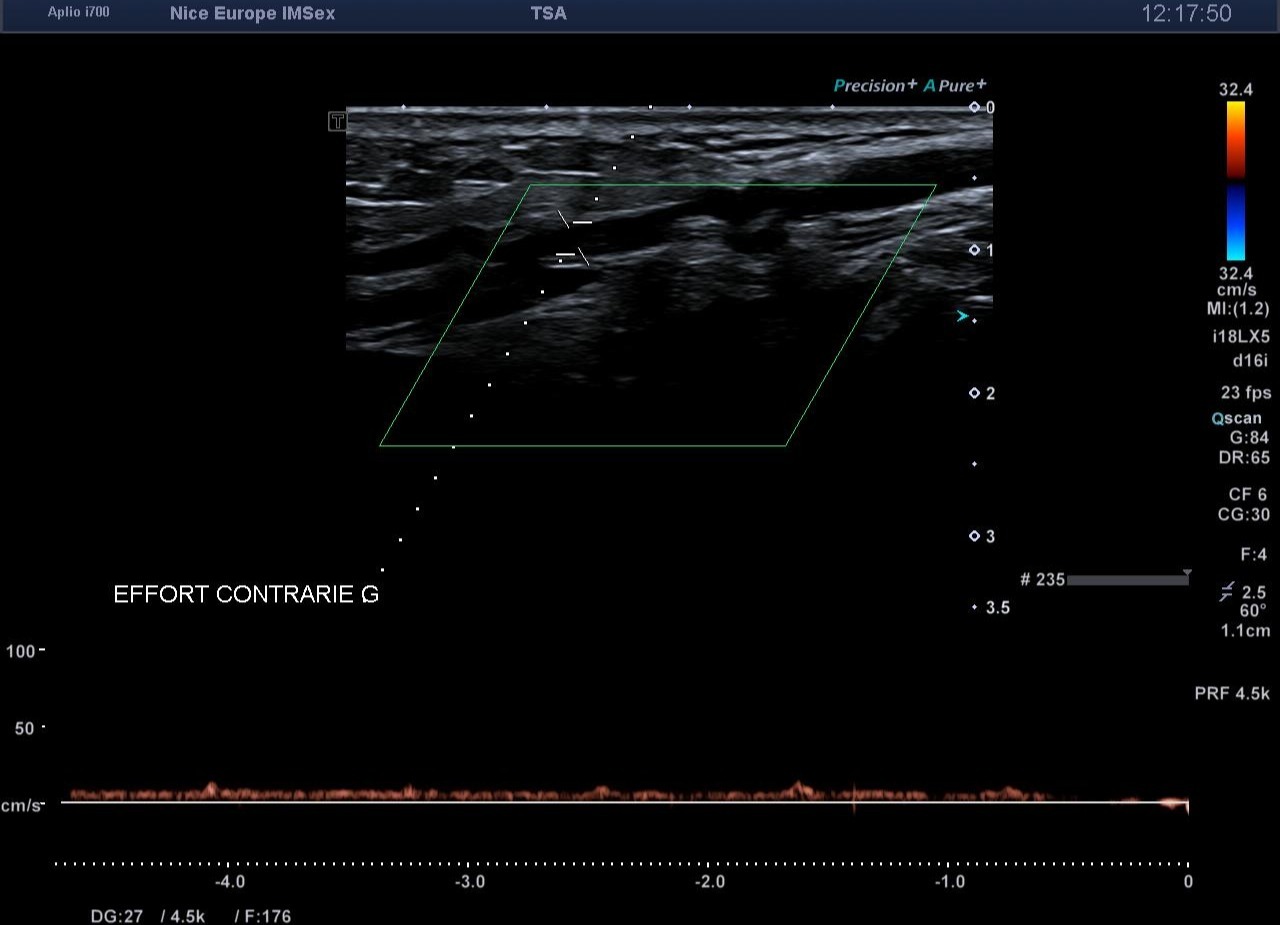

Devant ce morphotype athlétique et la négativité de l'examen statique, un test de provocation par échographie dynamique est entrepris pour rechercher un syndrome de l'artère poplitée piégée (ou piège poplité). Lors d’une manœuvre de flexion plantaire contrariée (mise en tension soutenue des muscles de la loge postérieure contre résistance), on objective en temps réel :

1. 1. Une compression extrinsèque majeure de l’artère poplitée par les chefs musculaires gastrocnémiens.

2. 2. Une occlusion artérielle complète (diastolique et systolique) au point de compression.

3. 3. Une abolition du flux artériel distal.

Pour confirmer de manière spécifique que l'occlusion siège bien au niveau du creux poplité, l'échographiste doit interroger l'artère tibiale antérieure (ATA). Cheminant dans la loge antérieure de la jambe, l'ATA est soustraite à l'hyperpression de la loge postérieure. Si le flux de l'ATA s'effondre lors de la flexion plantaire contrariée, cela atteste formellement que l'obstacle artériel se situe en amont, signant ainsi le piège poplité

• Spécificité du retentissement distal : L'arrêt du flux sur l'artère tibiale antérieure (ATA) lors des manœuvres de provocation est le témoin fiable et spécifique d'une occlusion poplitée extrinsèque.